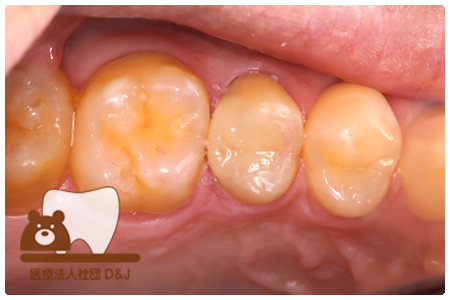

症例4フルジルコニアクラウン 左下6

治療前

治療後

37歳 男性

- 治療内容

- 以前のクラウンがセメントの劣化により外れた為その上にフルジルコニア製の被せ物を装着しました。見た目と強度を両立した自由診療の治療です。

- 治療期間

- 1カ月

- 費用

- 自費

フルジルコニアクラウン:77,000円(税込)

(R8.1月時点)

- その他の治療の費用は含まれておりません。

- リスク・副作用

- 硬い素材のため、かみ合う歯に負担がかかることがあります。将来取り外す場合に歯に負担がかかることがあります。強い力が加わると、まれに欠けたり割れたりすることがあります。